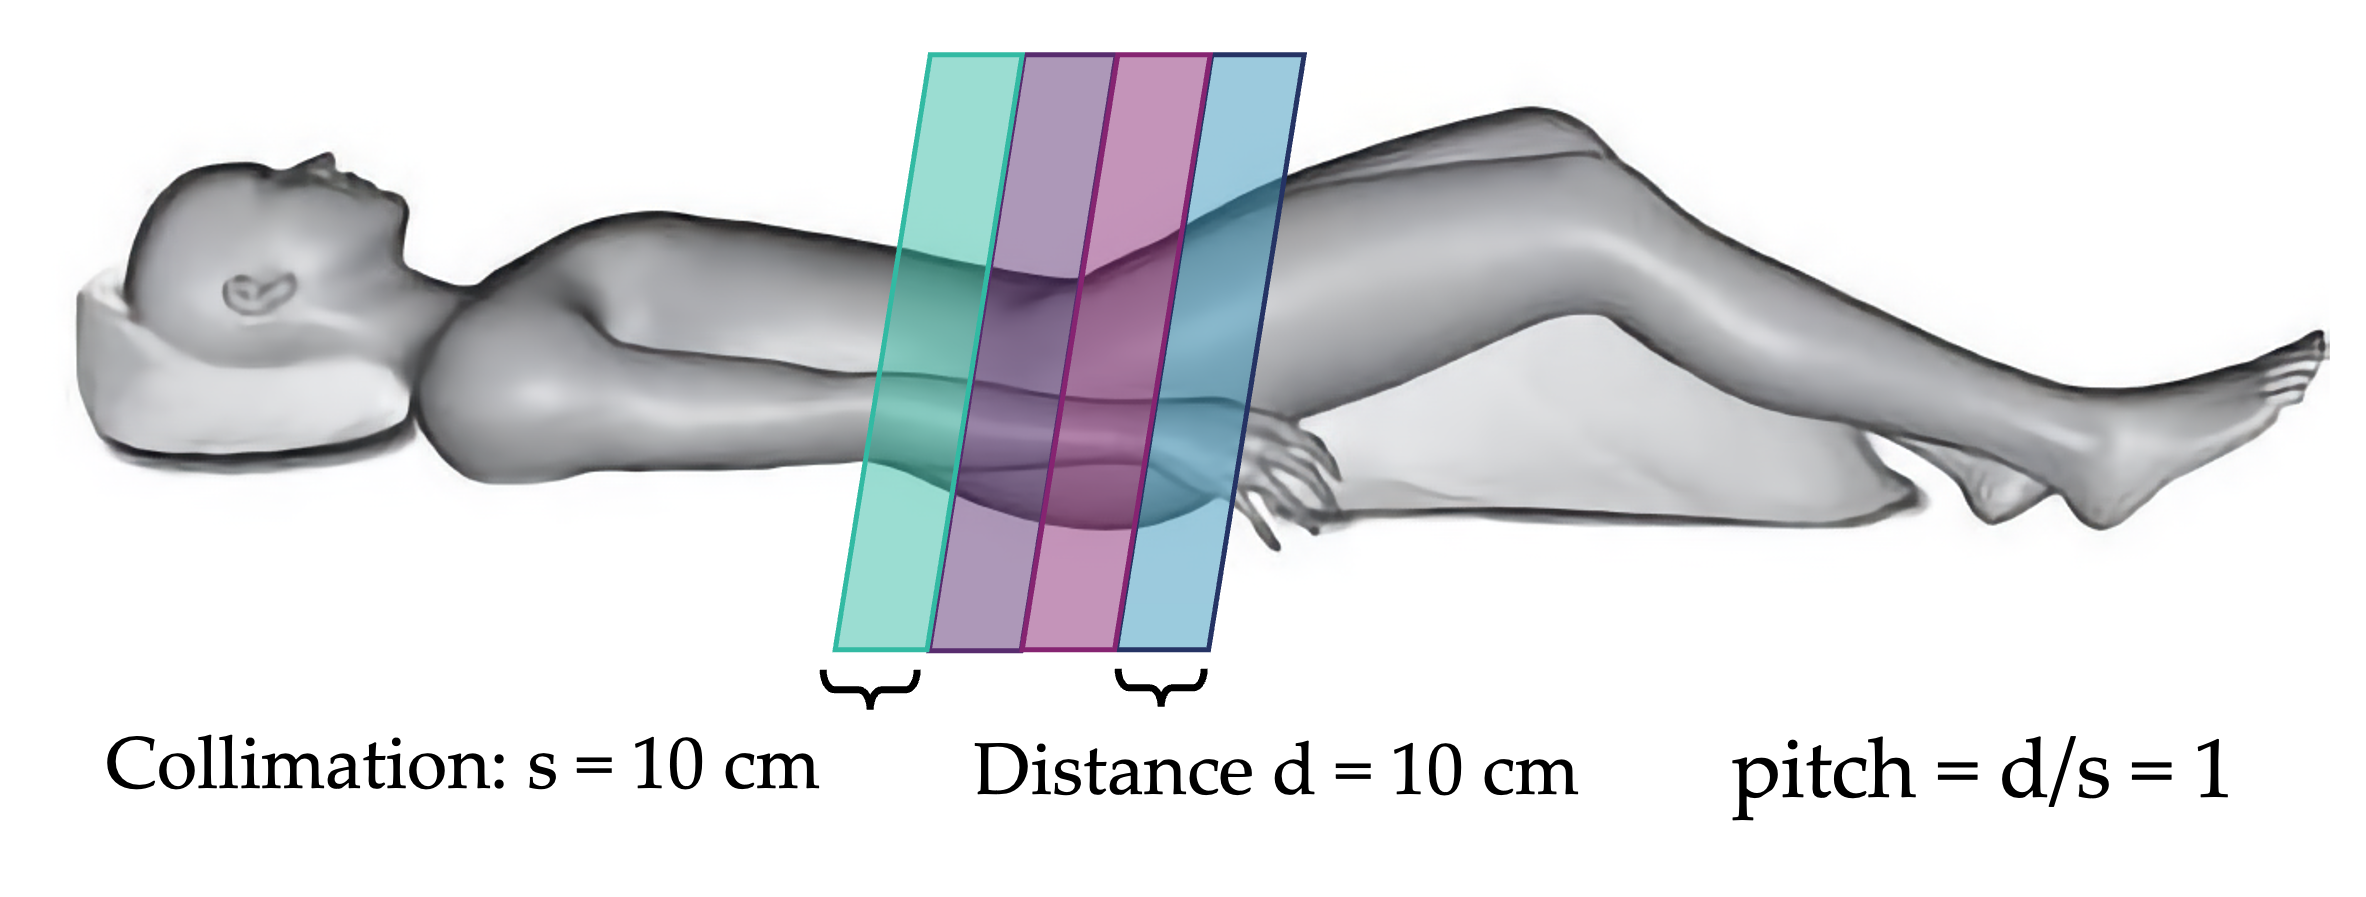

More commonly, modern CT scanners use a helical motion to acquire images. In this setup, the bed moves continuously while the tube-detector system rotate. This process results in faster imaging and greater dose control. The helical pitch determines the effective slice thickness and dose. Pitch is the distance the bed moves during one beam rotation, divided by the beam collimation. For overlapping motion, pitch is less than 1. Contiguous motion has pitch equal one, and extended motion has pitch greater than 1. The dose is roughly proportional to 1/pitch, such that higher pitches result in lower dose (less overlap). The final image slices are still axial and are reconstructed by averaging CT projections taken 180 degrees apart.

Question: if collimation is 10 cm and bed moves 20 cm per rotation, what is the pitch?

pitch = bed motion / collimation = 20 cm / 10 cm = 2 (extended)